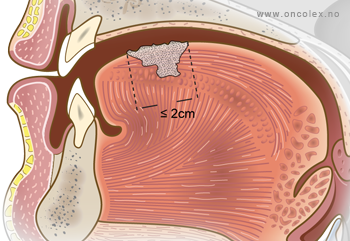

T1: Små svulster på 2 cm eller mindre i største diameter.

- T1 – små svulster på 2 cm eller mindre i største diameter